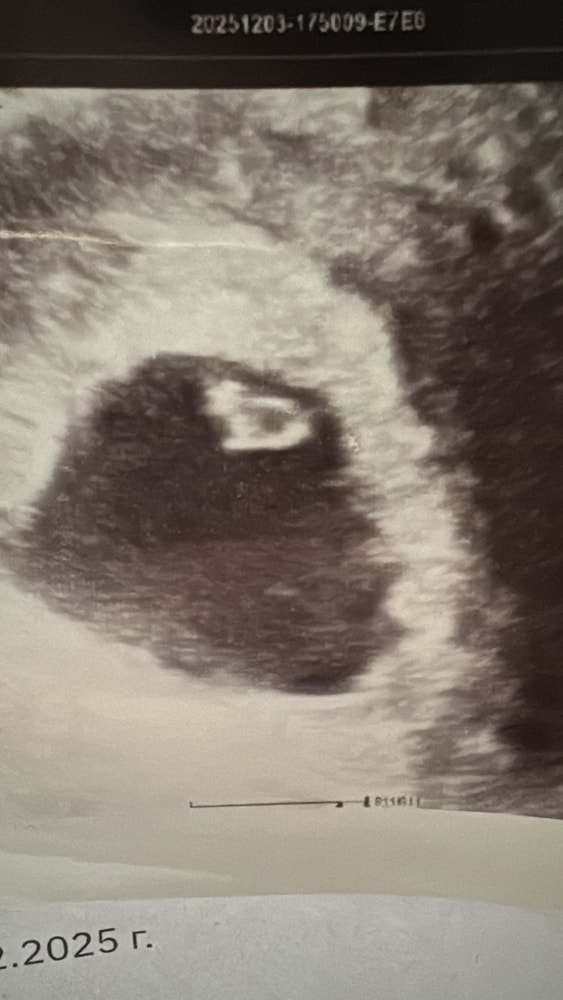

Хгч стремительно растет, нарастают симптомы токсикоза. Направляют на узи через неделю, прихожу сегодня и опять неопределенность. По акушерскому уже 7.4, вроде и мерцание видели, но долго держать датчик не стала узистка, якобы вредно и то, что было в прошлый раз у стенки стало «загагулиной слева» ох…

Увеличила сильно, сказала прийти еще дня через 3. Но через 3 дня уже пойду в мать и дитя, порекомендовали какого-то топового врача, надеюсь уже будет какая-то определенность, очень боюсь